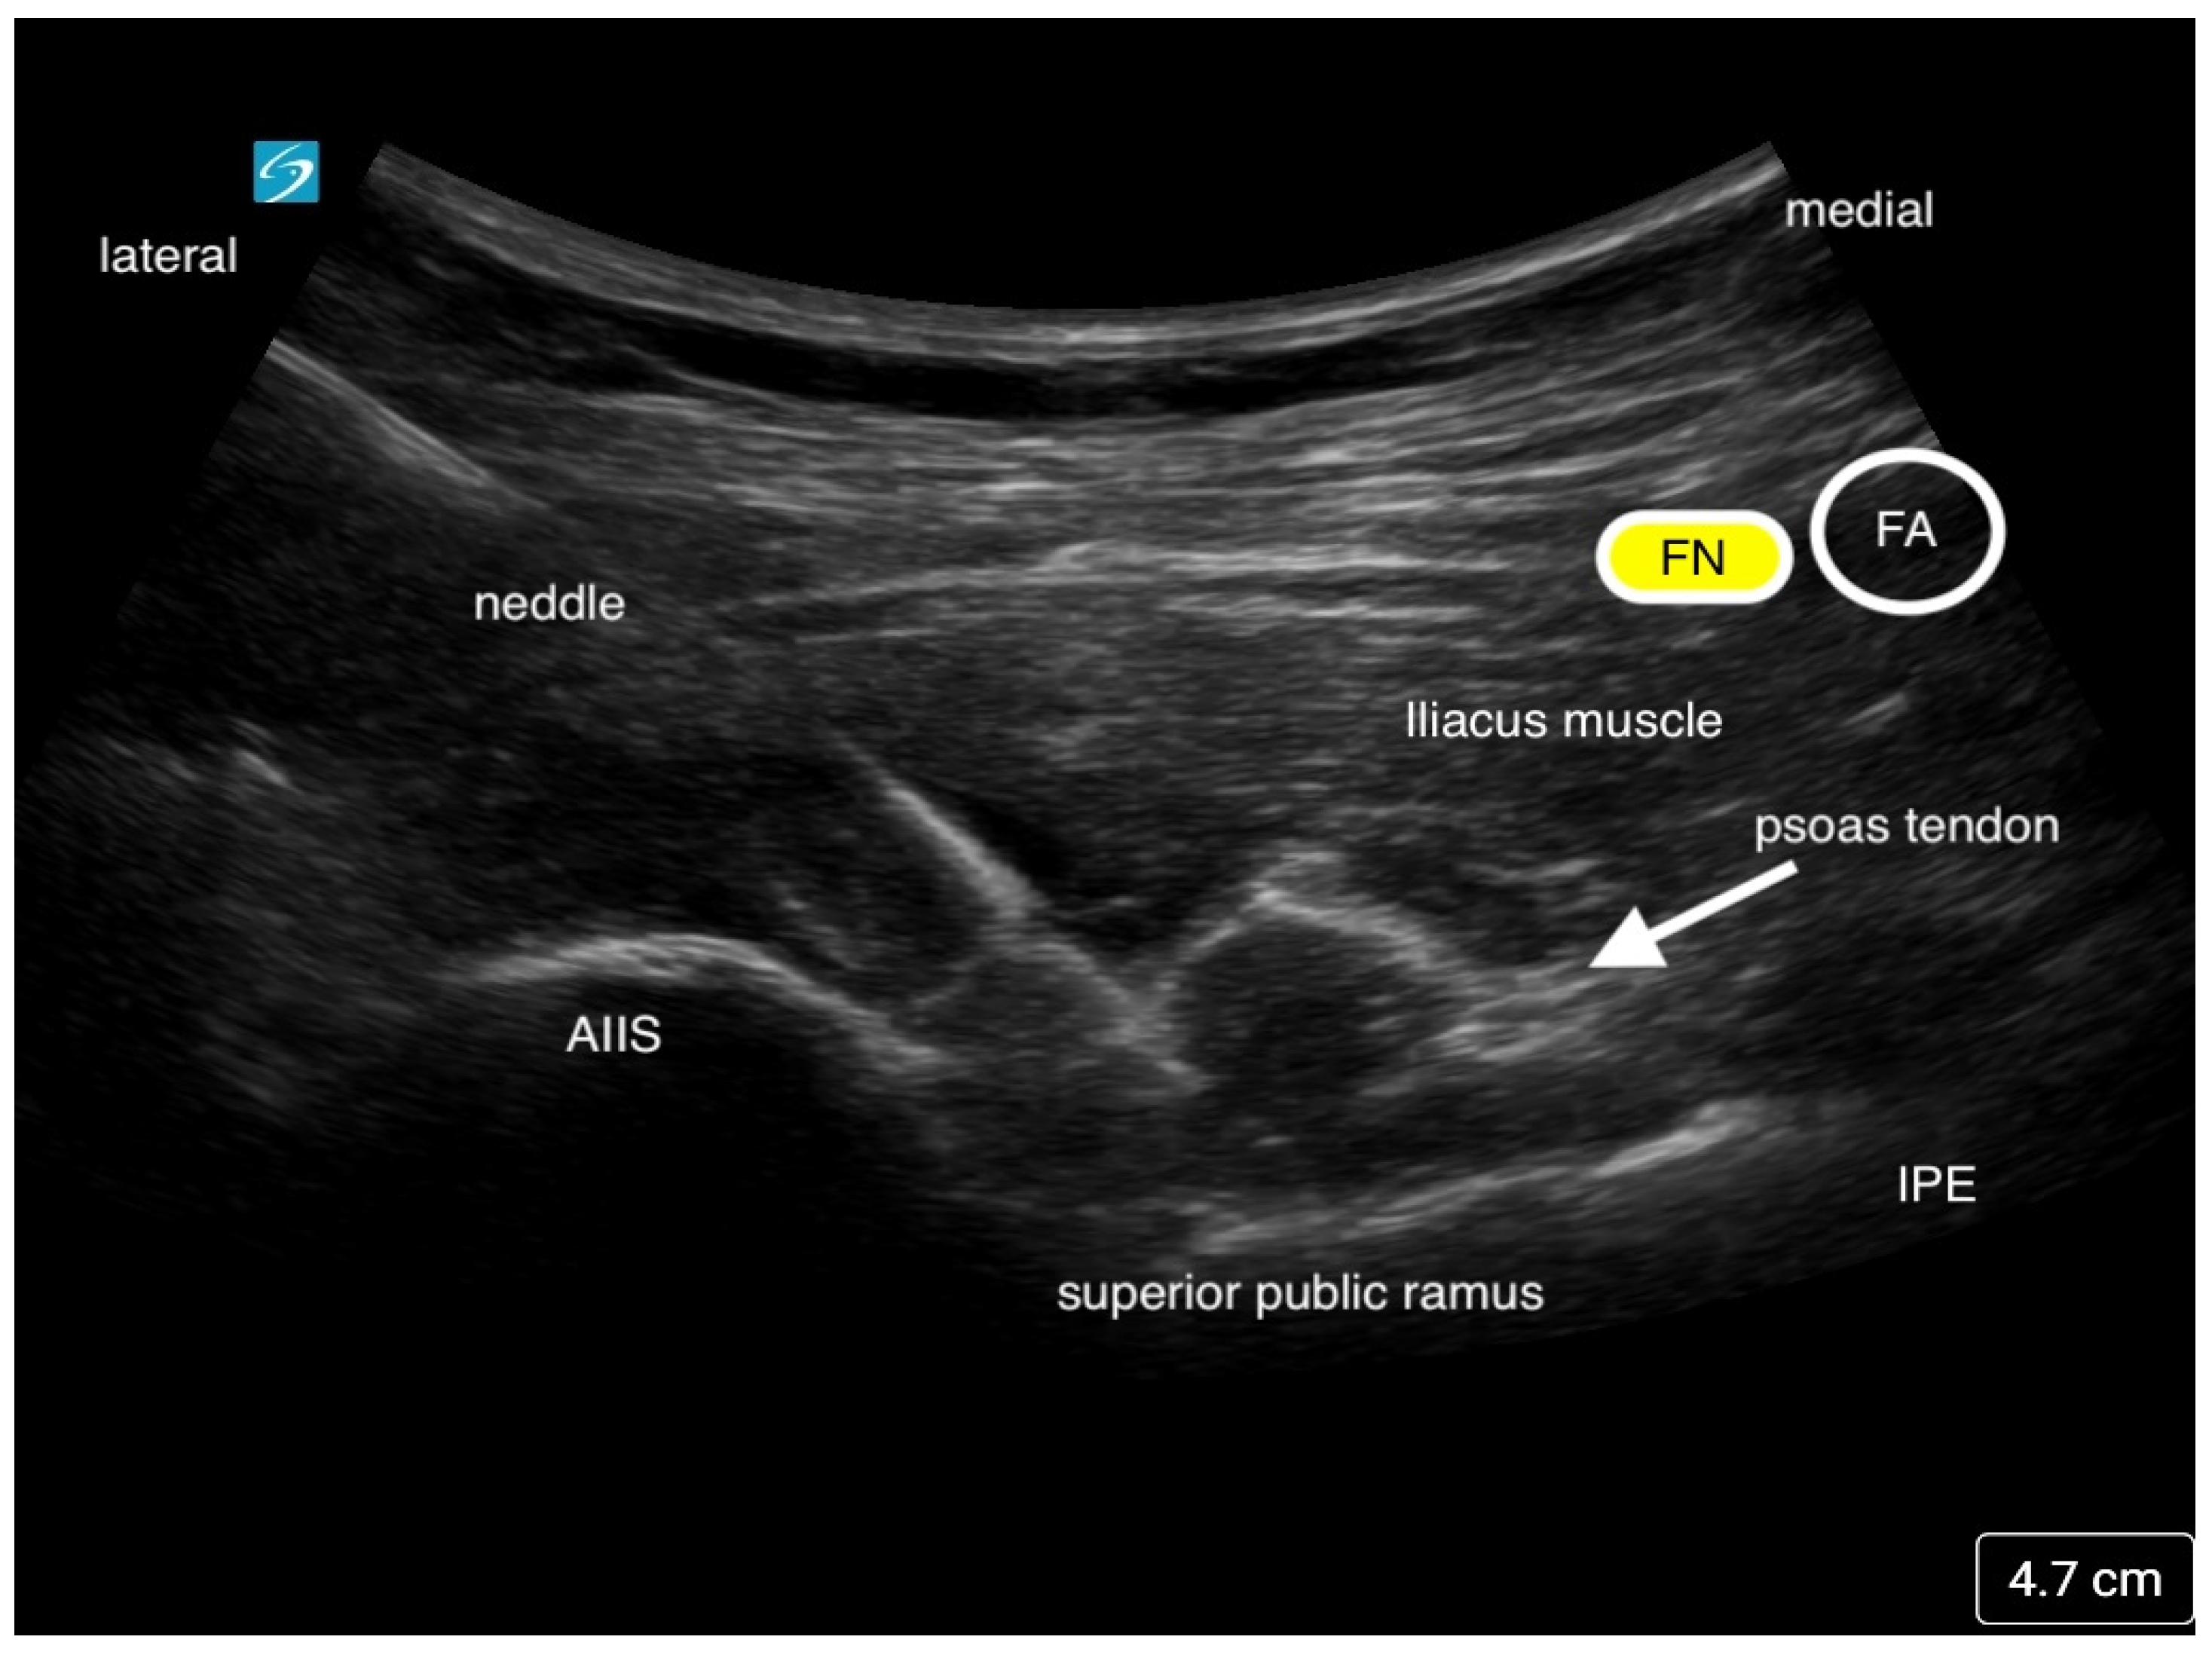

The Pericapsular Nerve Group (PENG) block is a fascial plane block that was developed by Giron-Arango et al. at Toronto Western Hospital and the University of Toronto to block the high articular branches of the femoral (FN), obturator (ON), and accessory obturator nerves (AON) to the hip joint [23]. These branches are mostly responsible for the nociceptive pain in the anterior and superolateral capsule of the hip joint. The FN and AON are often found between the anterior inferior iliac spine (AIIS) and the iliopubic eminence (IPE), thus making it easier to target both nerves. The block is performed with the patient in the supine position. Local anesthetic is deposited using a curvilinear low-frequency ultrasound probe with an in-plane technique from lateral to medial. The needle tip is placed in the fascial plane between the psoas tendon and the ilium (Figure 6) [23,24]. As described by Giron-Arango and colleagues, an optimal ultrasound image should include the AIIS, IPE, psoas tendon, iliopsoas muscle, and more superficially, the femoral neurovascular bundle [23]. Typically, 10–20 mL of local anesthetic is adequate to provide effective analgesia if there is fluid spread along the plane displacing the psoas muscle tendon.

Figure 6. This is an ultrasound image of the Pericapsular Nerve Group Block (PENG). Local anesthetic is injected below the psoas tendon. The needle approach is from lateral to medial. The femoral nerve (FN) and femoral artery (FA) is seen medially.

The authors would like to thank Kenneth Mullen for helping to obtain an image of a PENG block.